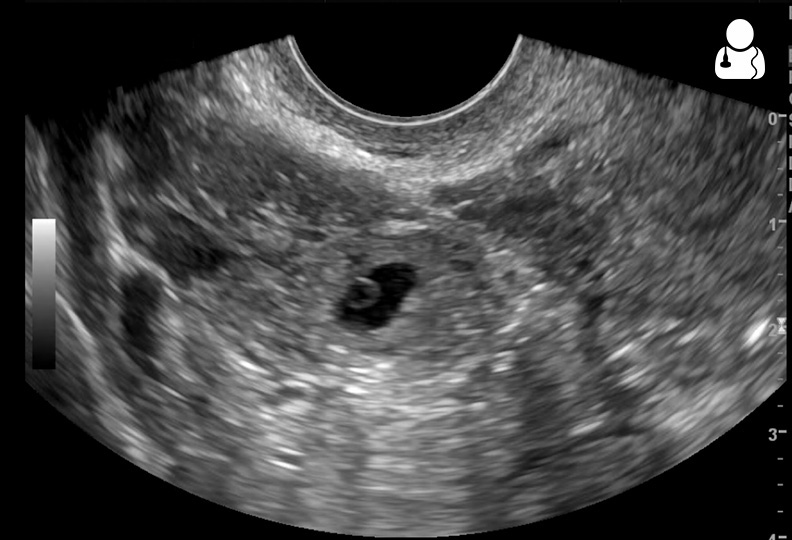

초음파 검사는 자궁외 임신 진단의 핵심적인 방법이다. 특히 질식 초음파 검사는 나팔관 내에 임신낭이 있고 태아 심장이 보이는 경우 자궁외 임신 진단에 매우 높은 특이성을 보인다. 이 검사는 질 내에 변환기를 삽입하여 진행하며[32], 자궁외 임신에 대해 최소 90%의 민감도를 가진다.[5]진단적 초음파 소견은 다음과 같다:

- 부속기 덩어리: 난소와 별도로 움직이는 덩어리가 관찰된다.

- 얼룩 징후 (Blob sign): 약 60%에서 보이는 비균질성 또는 비낭성 덩어리. 구형이 일반적이나 혈관 부종 시 관 모양일 수 있다. 민감도 84%, 특이도 99%로 추정된다.[5]

- 베이글 징후 (Bagel sign): 약 20%에서 보이는 비어 있는 자궁외 임신낭.[5]

- 임신낭 시각화: 약 20%에서는 난황낭이나 배아가 포함된 임신낭이 보인다.[5] 심장 활동이 보이면 "생존 가능한 자궁외 임신"이라 불린다.[5]

- 가성낭: 양성 임신 검사 결과에도 불구하고 자궁 내 임신이 아닌 액체 덩어리인 가성낭이 최대 20%의 여성에게서 나타날 수 있어 자궁외 임신 가능성을 배제할 수 없다.[5]

- 복강 내 액체: 직장자궁와에서 소량의 무에코성 액체는 자궁내 임신과 자궁외 임신 모두에서 흔히 발견된다.[5] 그러나 에코 발생성 액체(혈액 추정)는 자궁외 임신 여성의 28~56%에서 발견되며, 복강 내 혈종을 강력히 시사한다.[5] 이는 반드시 나팔관 파열이 아니며, 원위 나팔관 개구부 누출 결과일 수 있다.[5] 액체가 자궁저에 도달하거나 방광자궁와에 존재하면 의미있는 소견으로 간주된다.[5] 간신와에 액체가 보이면 심각한 복강 내 출혈의 표지자이다.[5]